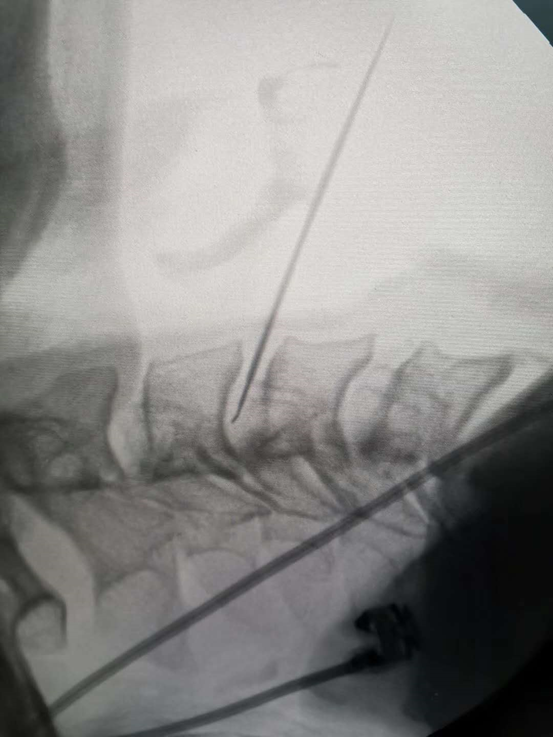

腰椎间盘突出症介入微创治疗 臭氧绿色疗法

脱出型腰椎间盘的介入治疗 随访片

只需30分钟 腰椎间盘突出微创介入治疗实拍